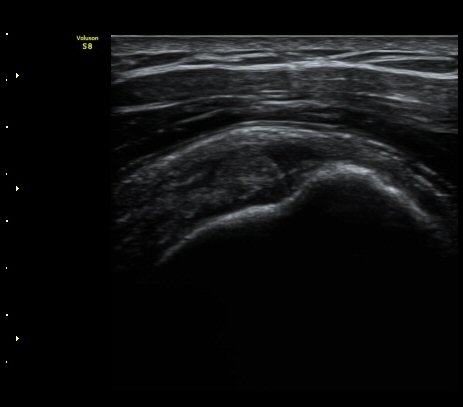

ÀÌµÎ¹Ú±Ù°Ç È¾´Ü¸é°Ë»ç¿¡¼­ ƯÀÌ ¼Ò°ß ¾øÀ½

(no specific abnormal findngs with transverse scan of biceps tendon) »çÁø 1, 2